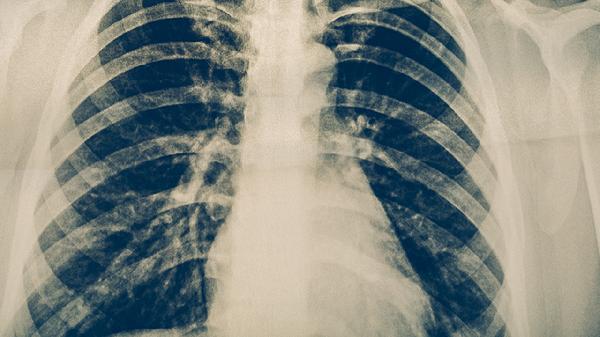

感冒通常由鼻病毒、冠状病毒非新型冠状病毒等引起,症状包括打喷嚏、流鼻涕、喉咙痛、轻微发热等,病程较短,一般一周内可自愈。新型冠状病毒感染则可能伴随更严重的症状,如持续高热、干咳、呼吸困难、乏力等,部分患者还会出现嗅觉或味觉丧失。两者的主要区别在于症状的严重程度和持续时间。

如果仅出现打喷嚏等轻微症状,且无明确的流行病学史如接触过确诊患者或到过高风险地区,则更可能是普通感冒。但如果症状持续加重,或出现呼吸困难、胸痛等严重表现,应及时就医并进行核酸检测以排除新型冠状病毒感染。